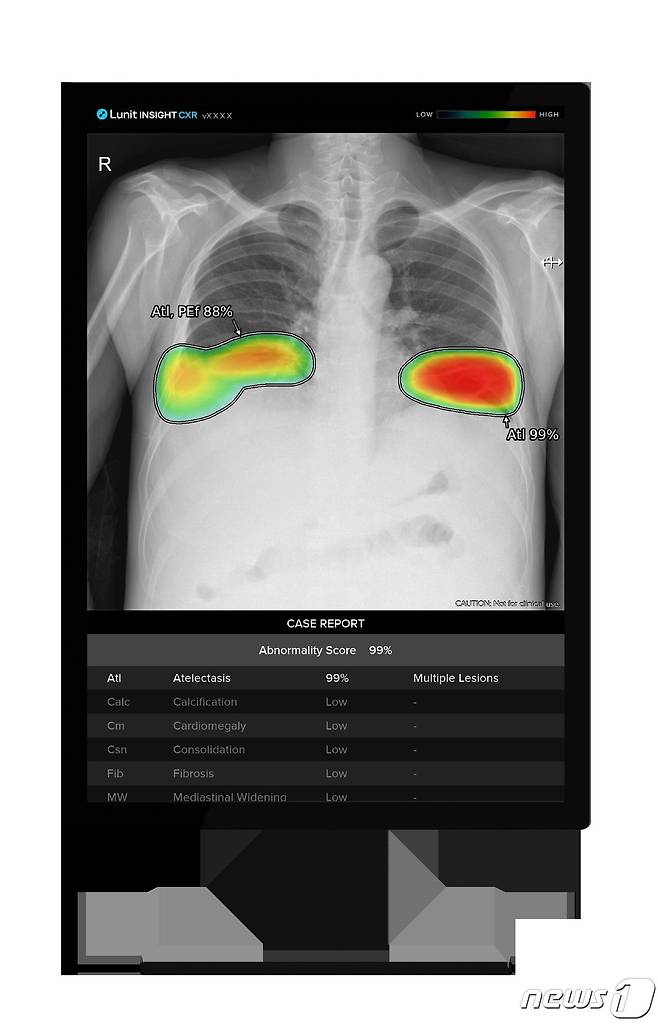

이번 계약에 따라 루닛은 흉부 엑스레이 AI 영상분석 솔루션 '루닛 인사이트 CXR'과 응급질환 AI 자동분류 솔루션 '루닛 인사이트 CXR 트리아지'를 삼성전자에 공급한다.

이번 계약에 따라 루닛은 흉부 엑스레이 AI 영상분석 솔루션 ‘루닛 인사이트 CXR’과 응급질환 AI 자동분류 솔루션 ‘루닛 인사이트 CXR 트리아지’를 삼성전자에 공급한다. 삼성전자는 프리미엄 이동형 및 고정형 엑스레이 촬영장비에 루닛 AI 솔루션을 설치해 해외 주요 국가에 판매할 예정이다.

루닛 인사이트 CXR은 흉부 엑스레이 영상에서 폐결절, 섬유화, 석회화 등 10가지 흉부 질환을 검출해 의료진의 진단을 보조하는 AI 솔루션이다. 루닛 인사이트 CXR 트리아지는 기흉, 흉수 등 응급 질환의 정상 및 비정상 소견을 자동분류하는 AI 솔루션으로 지난 2021년 11월 미국 식품의약국(FDA)의 허가를 획득했다.